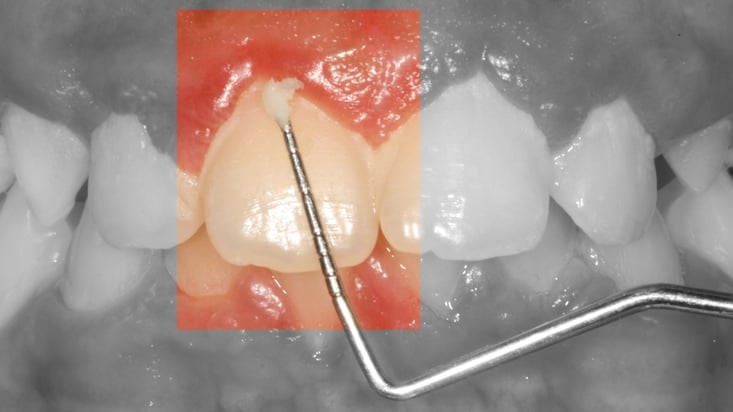

La plaque dentaire apparaît sous la forme d'un dépôt blanchâtre à la surface des dents.

Le fait d'associer le brossage des dents au repas tend à suggérer que la plaque dentaire correspond à un dépôt alimentaire. Il n'en est rien : la plaque dentaire consiste en une accumulation de bactéries sur la surface des dents.

Ces bactéries, selon le site dentaire auquel elles adhèrent, vont être responsables de la formation de caries ou du développement de maladies gingivales, telles que les gingivites et les parodontites.